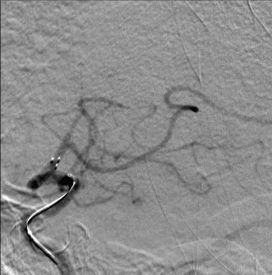

3. 颈内动脉C1段支架植入。

颈内动脉DSA提示颈内动脉狭窄,远端血流较差。 颈内动脉置入9mm-40mm Protege支架,收回保护伞后DSA提示血管再通良好,给予替罗非班7ml/h。 术后即刻查体NIHSS评分8分,给予替罗非班10ml/h泵入,持续24h。 术后第2天复查灌注成像提示双侧半球基本对称,CTA提示右侧颈内动脉以及大脑中动脉通畅。